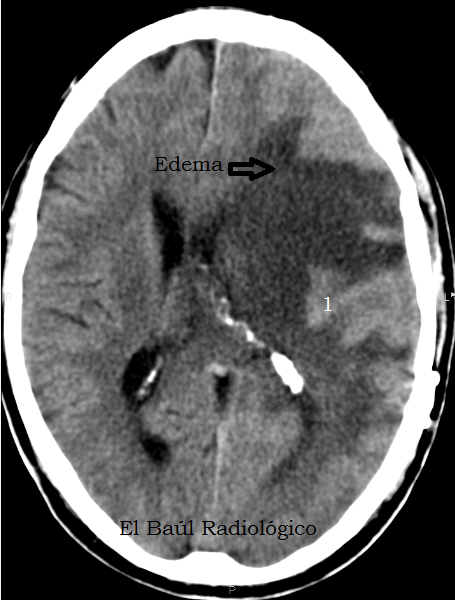

FIGURA 2) Corte más cefálico, con edema digitiforme. Suele asociarse a tumores malignos. ¿Podemos detectar con certeza la causa que lo ha producido? No.

(A more cephalad CT image, with digitiform edema. It is usually associated with malignant tumors. Can we identify, with certainty, the cause that has produced it? No)